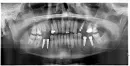

У меня 25-й зуб вырос под наклоном. 28-й зуб удалён. Через неделю должны уже установить мост. Вроде такая конструкция называется консоль.

Будет ли такая конструкция надёжная? Не будет ли эта консоль в процессе жевания упираться в 23-й клык? Возможна ли в моем случае установка мостовидного протеза на два опорных зуба 27-й и 25-й?

Можно сделать мостовидный протез с опорой на 25-й и 27-й зуб.